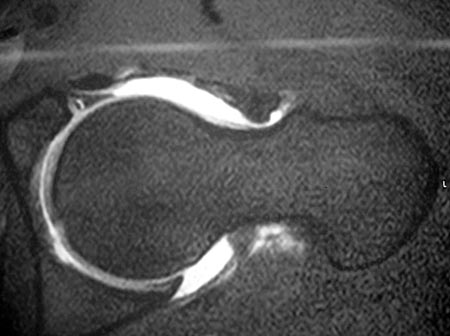

Todos los pacientes fueron estudiados con radiografías en posición de frente y “Cross table”, Tomografía Axial Computada, Resonancia Magnética Nuclear y Artroresonancia (Fig. 5 y 6).

Figura 5: Artroresonancia, corte axial. Lesión del Labrum./ Figura 6: Artroresonancia, corte coronal. Lesión del Labrum.